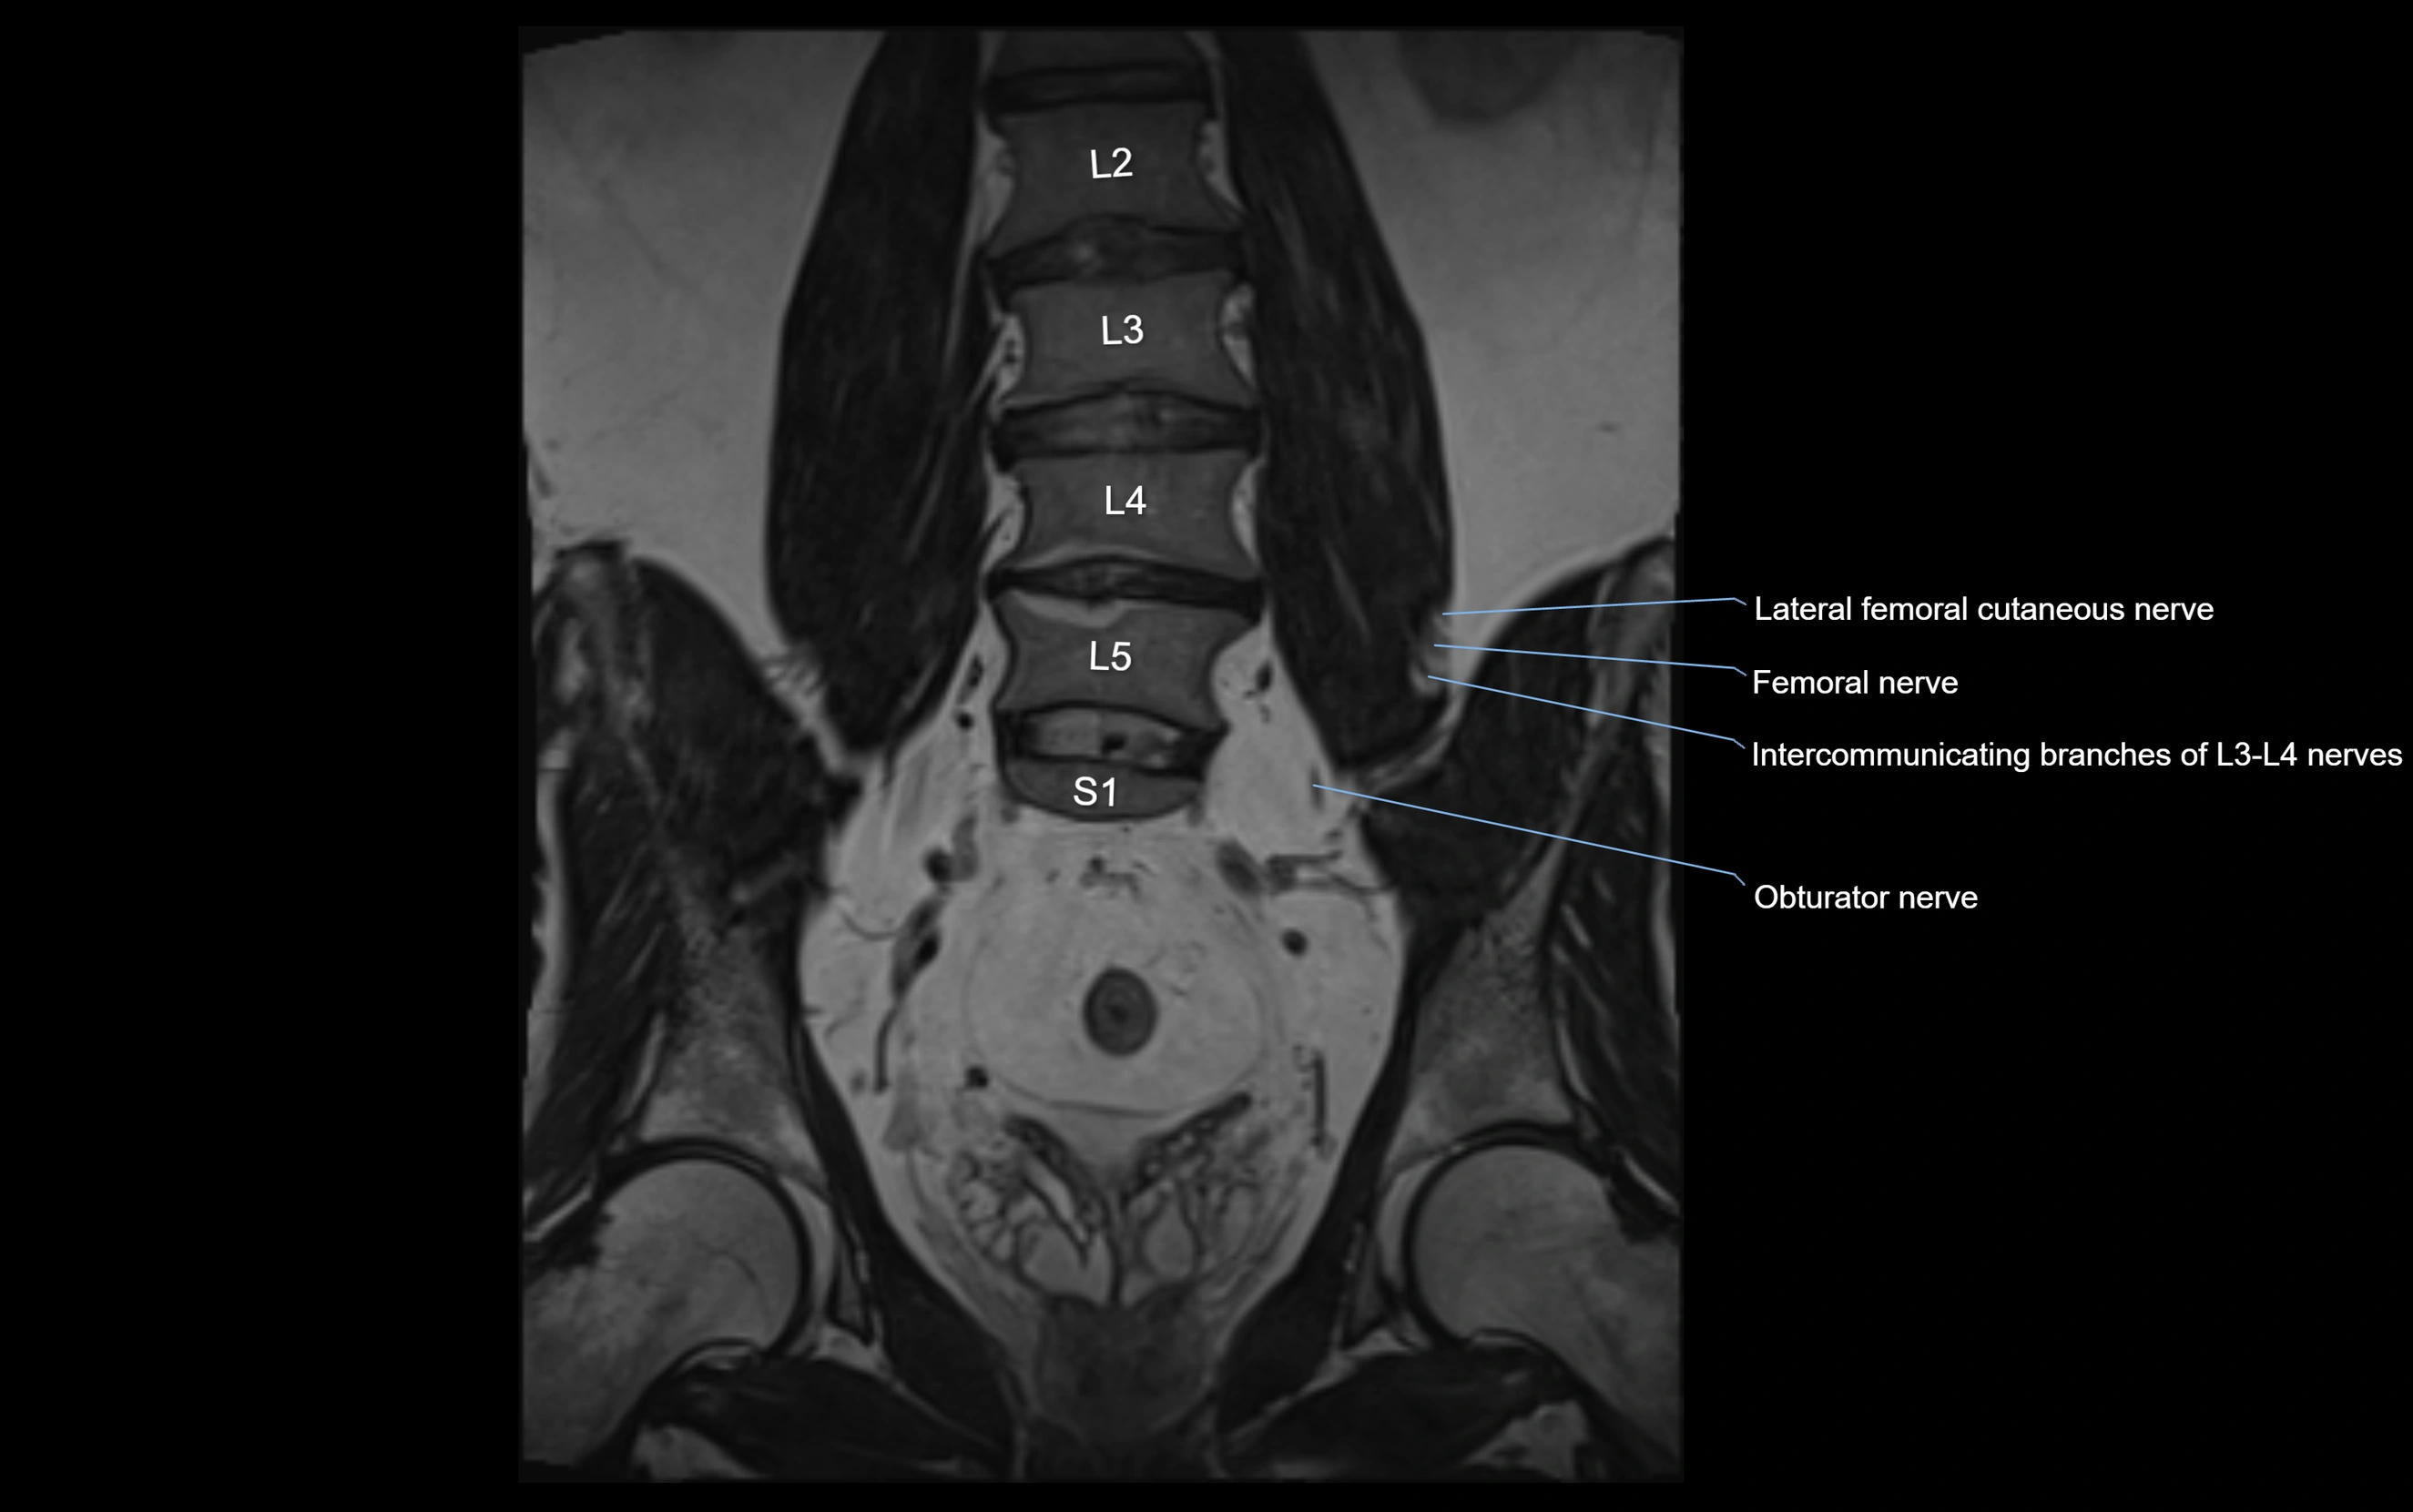

MRI image

image